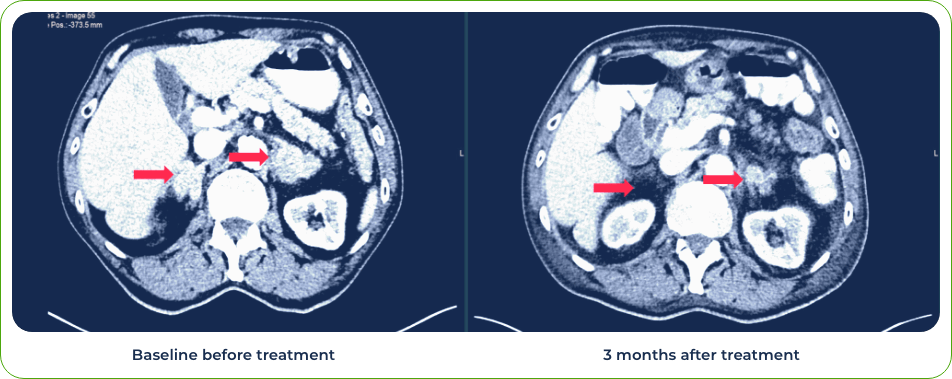

Diagnosis:

Stage IV Squamous Cell Carcinoma of Lung

Sites of metastases:

Spleen and liver